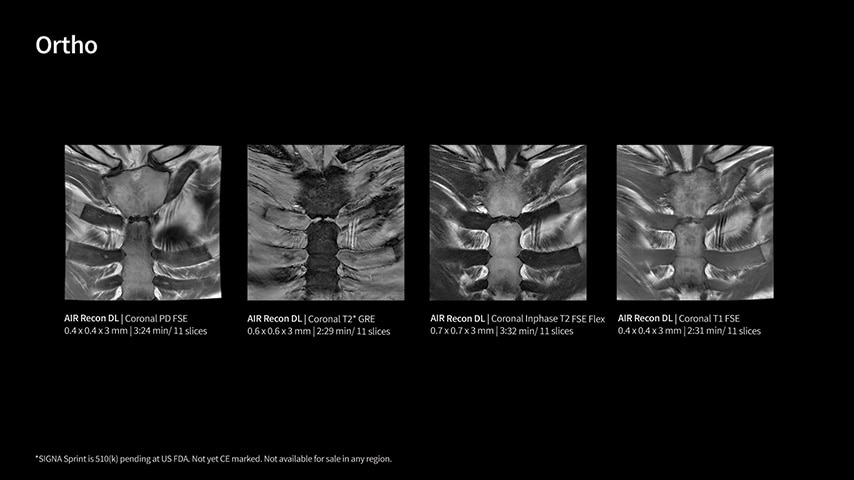

Imaging capabilities to unlock the power to explore further

The growing clinical need within oncology and cardiology requires an MRI scanner that can rise to the challenge. With a high gradient performance of 65/200, SIGNA Sprint helps deliver crystal-clear imaging for ultimate diagnostic confidence. Improved signal-to-noise ratio (SNR) and diffusion, with deep-learning solutions that could enhance diagnostics and treatment response monitoring in your oncology patients.¹ Additionally, the shift from qualitative to quantitative cardiac MRI reduces the time and expertise needed to interpret scans and offers greater consistency and reliability. Helping you to unlock the power to explore further - even in your most challenging cases.

With GE HealthCare's comprehensive suite of deep-learning solutions integrated into SIGNA Sprint, you can unlock the full potential of your MRI system. No need for complicated patient setups or imaging protocols. The exceptional intelligence of our AI solutions offer multiple benefits, with AIR Recon DL giving pin-sharp images, Sonic DL accelerating scans up to 12x, and AIR x enabling automated slice placement. All helping to enhance your department’s workflow efficiency, increase patient throughput, and get the diagnostic clarity you need, faster.¹ Meaning you can spend more time on what truly matters—personalized patient care, enabling optimized treatment plans and treatment response monitoring—ultimately, supporting better clinical outcomes.